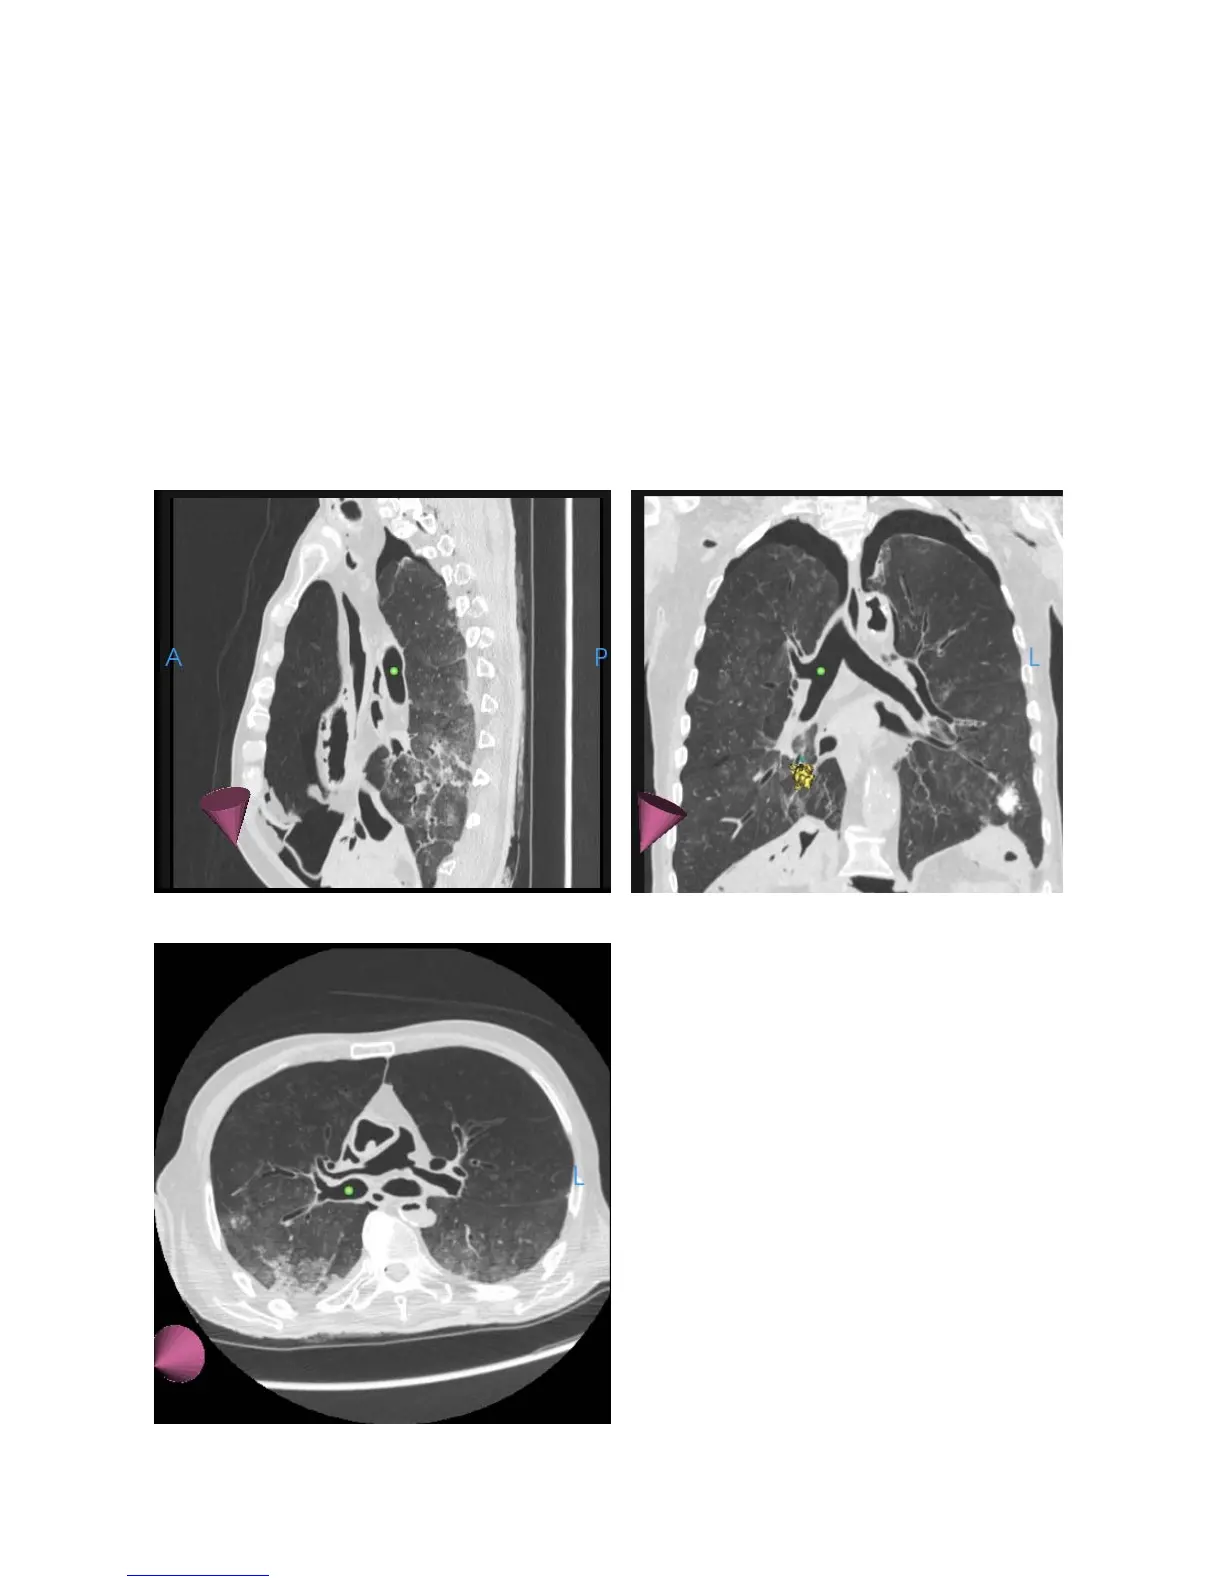

Axial, Sagittal, and Coronal CTs

In the following images, the axial, sagittal, and coronal slices of the CT scan at

the location of the scope tip appear. In these images, the scope tip is

represented by a green ball and the direction of the tip is represented by a purple

cone.

Sagittal

Coronal